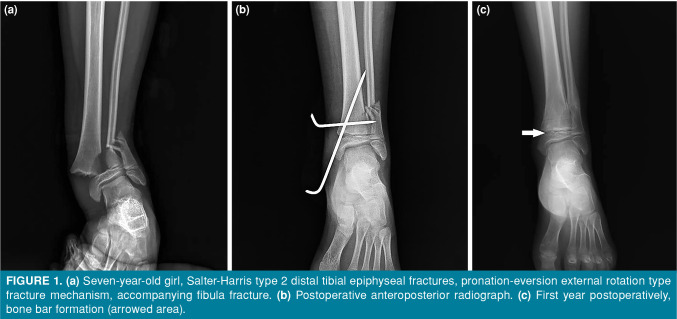

Patients and methods: Between January 2015 and January 2021, a total of 46 patients (37 males, 9 females; mean age: 11.9±2.5 years; range, 6 to 16 years) who were operated within 12 h due to displacement >2 mm after reduction were retrospectively analyzed. Demographics, fracture type (Salter-Harris [SH]), fracture mechanism (Dias & Tachdjian [DT]), accompanying fibula fracture, and initial displacement were assessed with preoperative radiographs. At two years of follow-up, PPC, angular deformity, and length discrepancy were evaluated.

Results: Of the patients, PPC was observed in 21.7%. Angular deformity and length discrepancy were noted in 6.5% of cases. The average initial displacement was 6.8 mm, with no significant correlation between displacement and complications (p>0.05). While the rates of PPC varied by fracture type, there was no statistically significant relationship between fracture types and the development of complications (p>0.05). Premature physeal closure was more common in fractures caused by the supination-plantar flexion (SPF) mechanism (60%) compared to the pronation-eversion external rotation (PEER) mechanism (5.3%) (p=0.018). Angular deformity and length discrepancy were only associated with SH type 3 and 4 fractures. Although fibular fractures accompanied 25% of distal tibial epiphyseal fractures, their presence did not show a significant correlation with complications (p>0.05).

Abstract Image